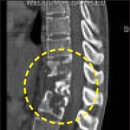

식은땀·식욕부진과 같은 몸살 기운이 나타난다. 그러다가 척추에 염증이 생기면서 허리 통증까지 겪는다. 강남세브란스병원 신경외과 김근수 교수는 "몸살 기운이 있으면서 허리를 굽혔다 펼 때 통증이 느껴진다면 척추결핵을 의심해볼 수 있다"며 "이때...